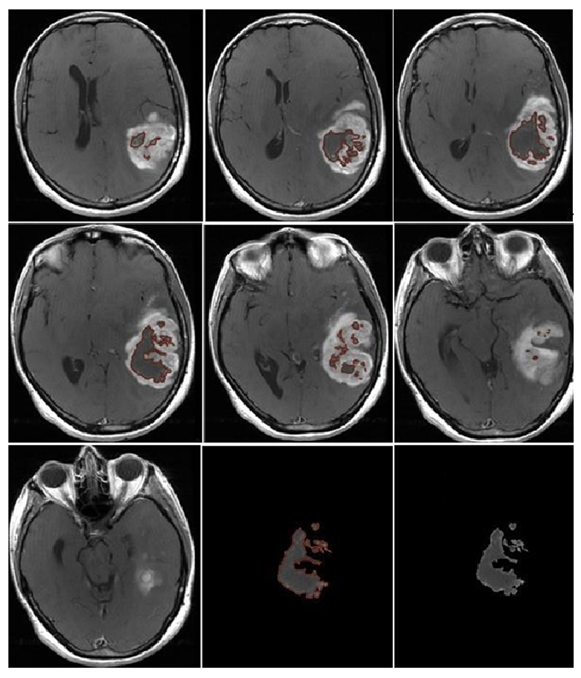

- Morphological appearance: We divided GB lesions into three categories based on the enhancing wall thickness: thin, <3 mm; thin-nodular, when the enhancing wall showed focal thickenings > 3 mm; and nodular, when solid appearance was predominant and intratumoral necrosis was absent or <1.5 cm3. A total of 11 (13%) masses showed a thin pattern, 51 (58%) showed a thin-nodular pattern, and 25 (29%) showed a nodular pattern.